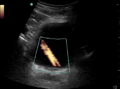

- May use power Doppler over the inferior border can demonstrate ureteral jets

- Ureteral jets can indicate patent ureter

- Twinkle Sign: Rapid alternation of color immediately behind a stationary echogenic object, acquiring a false appearance of movement in color Doppler mode